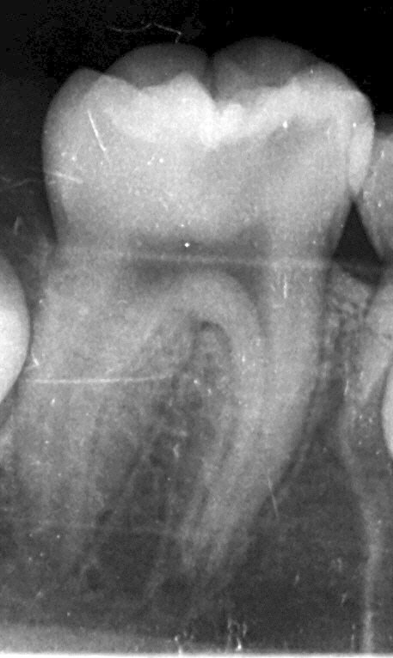

所見 右下臼歯に深いう蝕を認め、歯髄近接または露出の可能性が疑われた。

患者は9歳であり、当該永久歯は**歯根の形成途中(根未完成歯)**であった。

永久歯の正常な発育を考慮し、可能な限り歯髄の保存を目的として

生活歯髄温存療法を選択した。